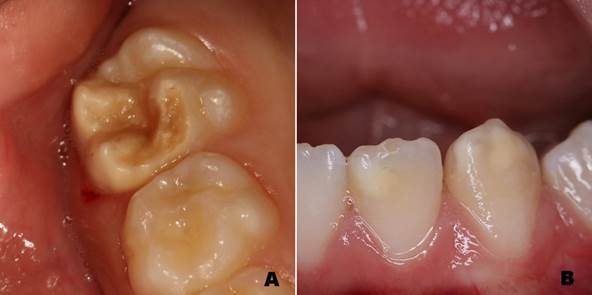

This cross-sectional study aimed to investigate the association between developmental defects of enamel (DDE) and single nucleotide polymorphisms (SNPs) in the genes encoding the vitamin D receptor (VDR) and parathyroid hormone (PTH). Orthodontic patients receiving treatment at a dental school were selected through convenience sampling. Intra-oral photographs were used to assess DDE, which were classified according to the criteria proposed by Ghanim et al. (2015) by a single calibrated examiner (Kappa>0.80). Enamel hypoplasia, molar-incisor hypomineralization (MIH), hypomimineralized second primary molar (HSPM), and non-MIH/HSPM demarcated opacities were considered for the analysis. Genomic DNA was extracted from buccal cells. The SNPs in VDR (rs7975232) and PHT (rs694, rs6256, and rs307247) were genotyped using real-time polymerase chain reactions (PCR). Statistical analyses were performed using the PLINK software (version 1.03, designed by Shaun Purcell, EUA). Chi-square or Fisher's exact tests were performed at a significance level of 5%. Ninety-one (n=91) patients (49 females and 42 males) (mean age of 14.1±5.8 years) were included. The frequency of DDE was 38.5% (35 patients). Genotype distributions were in Hardy-Weinberg equilibrium. No significant statistical association was found between DDE and the SNPs evaluated. A borderline association (p=0.09) was observed between DDE and the CC haplotype for SNP rs7975232 in VDR. In conclusion, the selected SNPs in VDR and PTH genes were not associated with DDE in the studied samples.